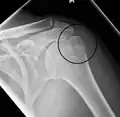

Proximal humerus fracture